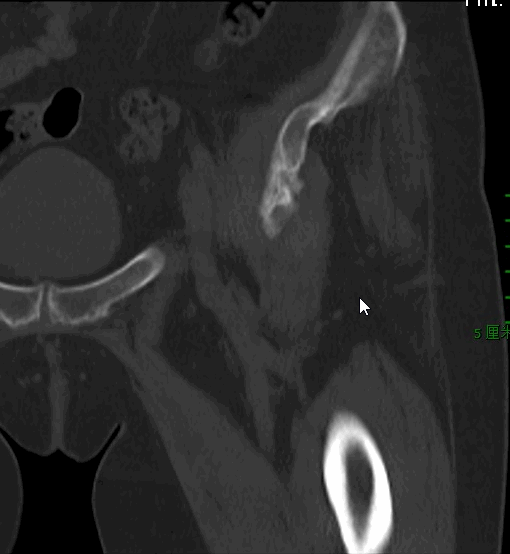

W女士,13年前因髋臼骨折行内固定手术,近2年来左髋部间断疼痛并活动受限、跛行,拟行人工髋关节置换术。

另外,对于肢体短缩、屈曲挛缩的病例,前路关节置换复位过程比后路要容易得多,同时减少了牵引过程中对坐骨神经的牵拉。点击下图查看复位难易程度: